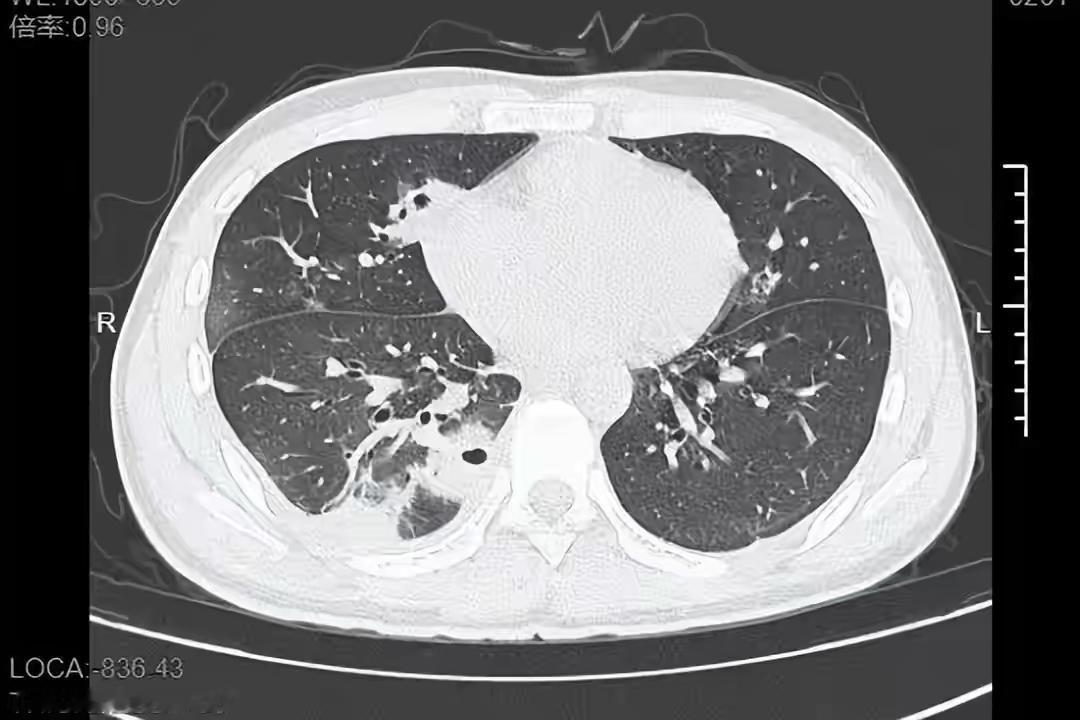

悲剧了!20岁大学生嫌脸上痘痘难看,以为挤掉能快点好,结果,痘痘依旧化脓了,甚至引发高烧,住进了ICU,医生安排CT检查,发现小林肺里有十几个空洞,部分肺组织已经坏死!网友:不知、不知道,一知吓一跳,我都不知道挤了多少个痘痘! 这事儿听着就吓人,谁能想到挤个痘痘能闹到进ICU的地步。小林这情况,医生后来解释说,是因为他挤痘痘的时候,手上的细菌顺着破损的皮肤钻进了血管,一路感染到了肺部,引发了严重的脓毒症。脸上的痘痘看着小,可位置特殊,尤其是鼻子周围那片“危险三角区”,血管直接连着大脑,一旦感染扩散,后果真能要命。 说起来,好多人都有挤痘痘的习惯。对着镜子看到那颗红红的疙瘩,总觉得手痒痒,挤完那一刻还挺有成就感。可很少有人想过,自己的手一天摸这摸那,细菌多着呢,挤的时候稍微没注意,就可能把细菌推进皮肤深层。而且挤痘痘本身就容易把毛囊挤破,让炎症更厉害,本来几天能好的痘,说不定挤完反而肿成大包,留疤都是轻的。 小林这案例算是给所有人提了个醒:脸上的痘痘真不是随便能碰的。尤其是那种又红又肿、摸着还疼的,十有八九是有炎症,这时候挤就是火上浇油。年轻人爱美心切能理解,但比起一时的痛快,还是得讲究方法。长了痘,注意清洁,饮食清淡点,实在严重就去看医生,配点药膏或者口服药,都比自己瞎折腾强。 现在好多人对皮肤问题的认知还停留在“挤挤就好”的层面,觉得医生说的“危险”是小题大做。可真等出事了才明白,身体这台机器精密着呢,一点小伤口处理不好,都可能引发连锁反应。就像小林,本来只是想让脸好看点,结果差点把命搭进去,这教训太深刻了。 各位读者你们怎么看?欢迎在评论区讨论。